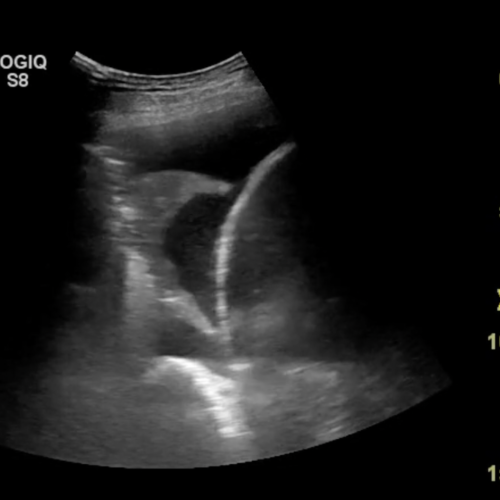

Projektet ønsker at forbedre behandlingen for patienter med væske mellem lungehinderne i akutafdelingen

Formålet med projektet er at undersøge to forskellige behandlingsmetoder til udtømning af væske mellem lungehinderne og metodernes effekt på tid til komplet udtømning af væske, den samlede indlæggelsestid samt symptomlindring hos patienter i akutafdelingen.